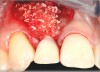

Fig 10. Case 2: Missing tooth No. 7 was extracted 3 months before implant placement.

Figure 10

Fig 11. A horizontal releasing incision across the edentate ridge; it terminates 1 mm from the adjacent teeth.

Figure 11